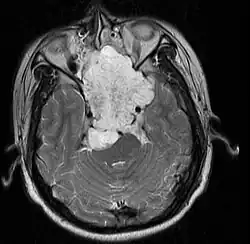

• Skull base:

• May be intracranial or extracranial, with mass effect symptoms depending on location

• Headaches and/or facial pain are common

• Pituitary insufficiency, hemianopsia/diplopia, cranial nerve deficits, nasal stuffiness.

• Maximal resection followed by proton beam irradiation.

• Overall survival is dependent upon local control of disease. Prognostic factor for local control of disease is amount of residual tumor after original surgery (<25cc residual tumor is better).

• Clear margins are achieved in <50% of skull base chordomas.

• Doses of 70 CGE necessary for control of residual disease.

• Institut Curie; 2005 (1992-2002) PMID 16227160 -- "Chordomas of the base of the skull and upper cervical spine. One hundred patients irradiated by a 3D conformal technique combining photon and proton beams." Noel G et al. Acta Oncol. 2005;44(7):700-8.

• Retrospective. 100 patients w/ skull base or upper cervical spine chordoma tx'd w/ proton/photon therapy. Median total dose to tumor 67 CGE.

• 2 yr local control rate 86.3%, 4 yr local control rate 53.8%.

• Multivariate analysis showed minimal dose to tumor <56 CGE and failure to encompass 95% tumor w/ 95% isodose line were independent factors for local control.